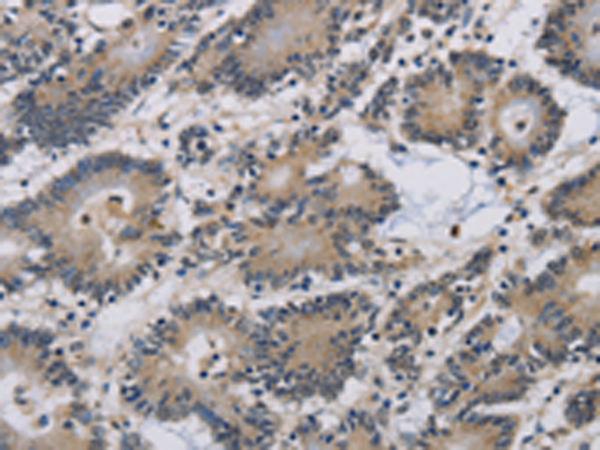

分类: 科研抗体货号: P04969别名: IMB1; IPO1; IPOB; Impnb; NTF97应用: IHC反应种属: Human, Mouse, Rat